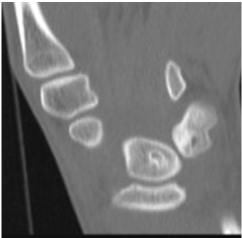

Plain radiographs, computed tomography (CT) and magnetic resonance imaging (MRI) findings revealed multifocal intra-osseous cysts and lunotriquetral AVN (Figure 1, Figure 2 and Figure 3).

Figure 2: CT confirms lytic areas with sclerotic margins. View Figure 2

As shown with this patient's CT scan, intraosseous cysts are observed in patients with SLE, however there is no evidence to suggest that the presence of intraosseous cysts leads onto AVN. Only one of 16 patients in a case series of intraosseous cysts secondary to SLE developed AVN [12]. All 16 cases were concomitantly being treated with corticosteroids and so a confounding factor when considering aetiological causes of AVN.